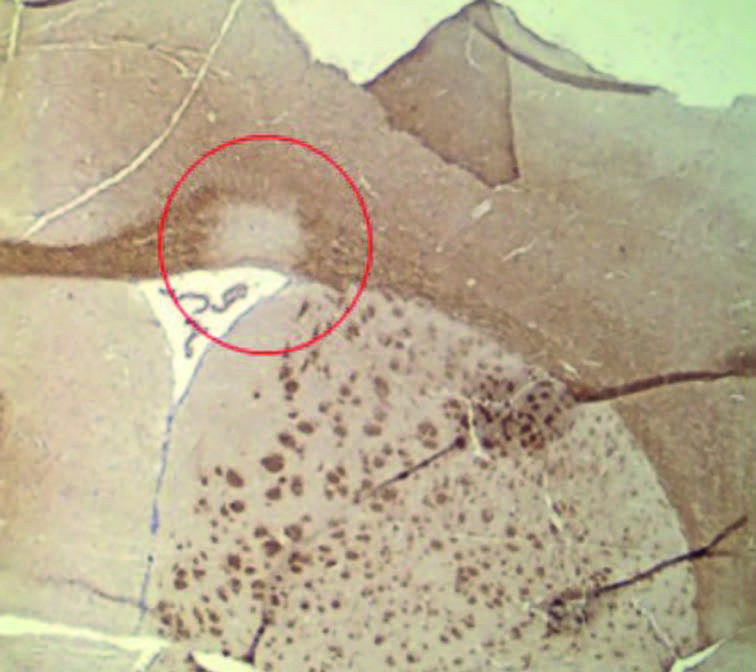

Representative images oLPC (L-α-Lysophosphatidylcholine) is injected locally into the brain of the mouse, inducing demyelinating lesions in a specific region. The resulting dysfunction and remyelination can be subsequently assessed and analysed. Depending on the injection site, de- and remyelination can be studied in different anatomical regions of the mouse CNS.

The red circle in the figure displays corpus callosum demyelination, 7 days post injection at a time point that the myelin debris has been cleared by the phagocytes and remyelination is not yet visible. The timing after the injection determines whether phagocytes are present in the lesion (demyelination) or whether OPCs are infiltrating to study remyelination.